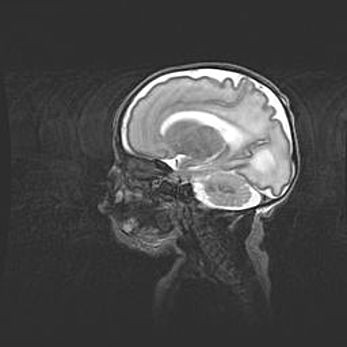

Аномалия Денди-Уокера. Признаки гипоплазии мозолистого тела.

Возраст: 5 месяцев 3 дня

Вес: 5550 г

Пол: мужской

Окружность головы: 39 см

Срок гестации: 40 недель

Аномалия Денди-Уокера – это порок развития головного мозга, для которого характерна триада симптомов: гипотрофия или аплазия червя мозжечка и/или полушарий мозжечка, расширение четвёртого желудочка с формированием ликворной кисты задней черепной ямки, гипертензионная гидроцефалия различной степени.

Гипоплазия мозолистого тела относится к дефектам внутриутробного этапа развития мозговой ткани, возникающим в процессе закладки структур головного мозга, что происходит на начальных этапах развития эмбриона.